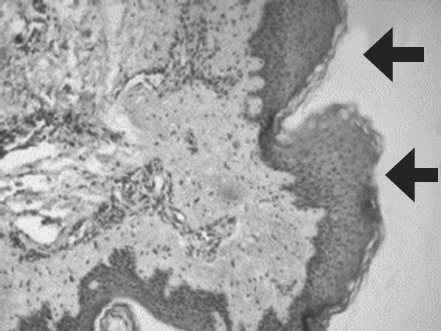

Histological examination of biopsy samples taken from the area of ATMSC transplantation for all the patients revealed the presence of pronounced vascularization with the perifocal proliferation of fibroblasts in both the superficial and deep layers of the dermis (Fig. 6, 7). An immunohistochemical study revealed that the use of ATMSCs resulted in a 5.6-fold increase in the expression of proliferation markers of epithelial and connective tissue cell lines in the injection area (p < 0.01) (proliferation 2.1–2.2), and that apoptotic activity was completely suppressed (Fig. 8, 9). Laser Doppler flowmetry assessment of the microcirculation in the area of stem cell injection on day 7 after early necrectomy, skin grafting, and the administration of MMSCTM showed double the average level of perfusion and mean square deviation of the amplitude of blood flow oscillations than for areas where MMSCTM was not used (p < 0.05) (Table 6).

Fig. 6. Patient D., 34 year sold, 5th day of observation. Active marginal epithelization. A wide band of the forming epidermal layer. Color in gof hematoxylin-eosin. Zoom ×400

Рис. 6. Пациент Г., 34 года, 5-е сутки наблюдения. Активная краевая эпителизация. Широкая полоса формирующегося эпидермального слоя. Окраска гематоксилином и эозином. Увеличение ×400